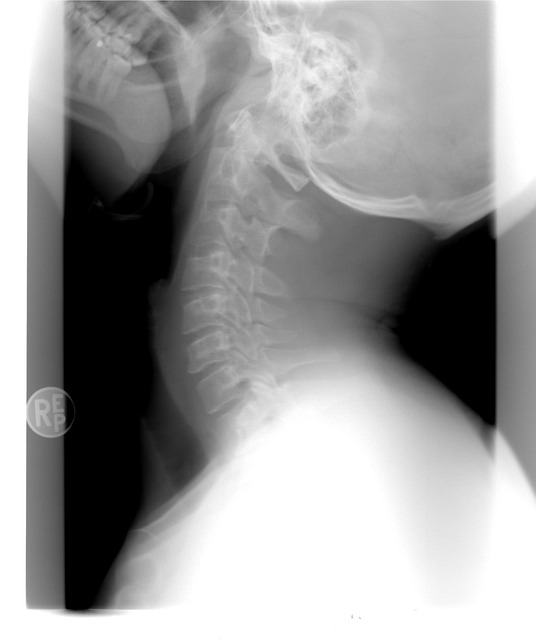

Diagnostic Imaging

Diagnostic imaging, such as X-rays, MRI scans, and CT scans, can help doctors identify the type and severity of car accident back injuries. These imaging tests provide detailed images of the spine and surrounding structures, allowing doctors to assess any damage and plan appropriate treatment.